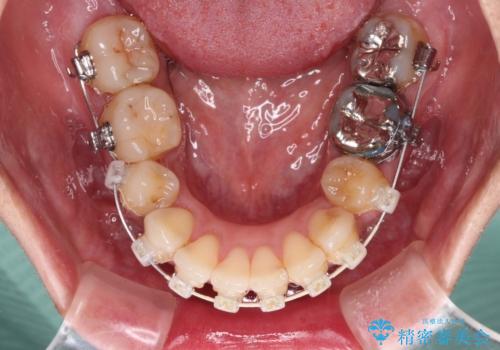

- 矯正装置

- 審美装置

- 治療期間

- 2年3ヶ月

- 歯列全体が内側に倒れ込んでいることと、口元の突出感を気にして来院された患者様です。

上下ともに歯列が狭窄しており、前方に突出している状態でした。

歯が重なるような叢生も認められたため、上下左右の第一小臼歯4本を抜歯して、口元が引っ込むように治療を行うこととしました。